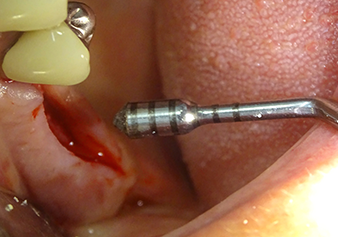

The I2A instrument (diameter 2.0 mm) was then used to perforate the sinus floor intermittently and on the smallest scale possible. This special piezosurgical method ensures that the Schneiderian membrane is not damaged. When the Z25P was used, the membrane was already lifted slightly by the coolant supplied via the instrument tip (Fig. 3). The coolant quantity was just 50% in order to avoid high pressure in the implant bed.

The Schneiderian membrane is carefully detached with the Z25P instrument (phase 1)

Fig.3: Following marking of the implant position and initial expansion of the bed, the Schneiderian membrane is carefully detached with the Z25P instrument (phase 1).